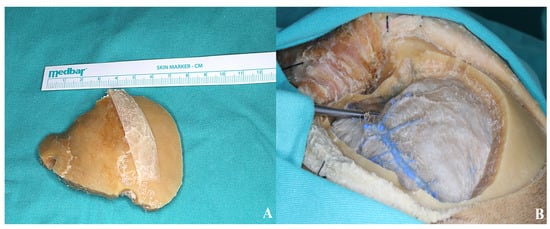

3.1.3. Craniotomy

3.1.4. Basal Drilling